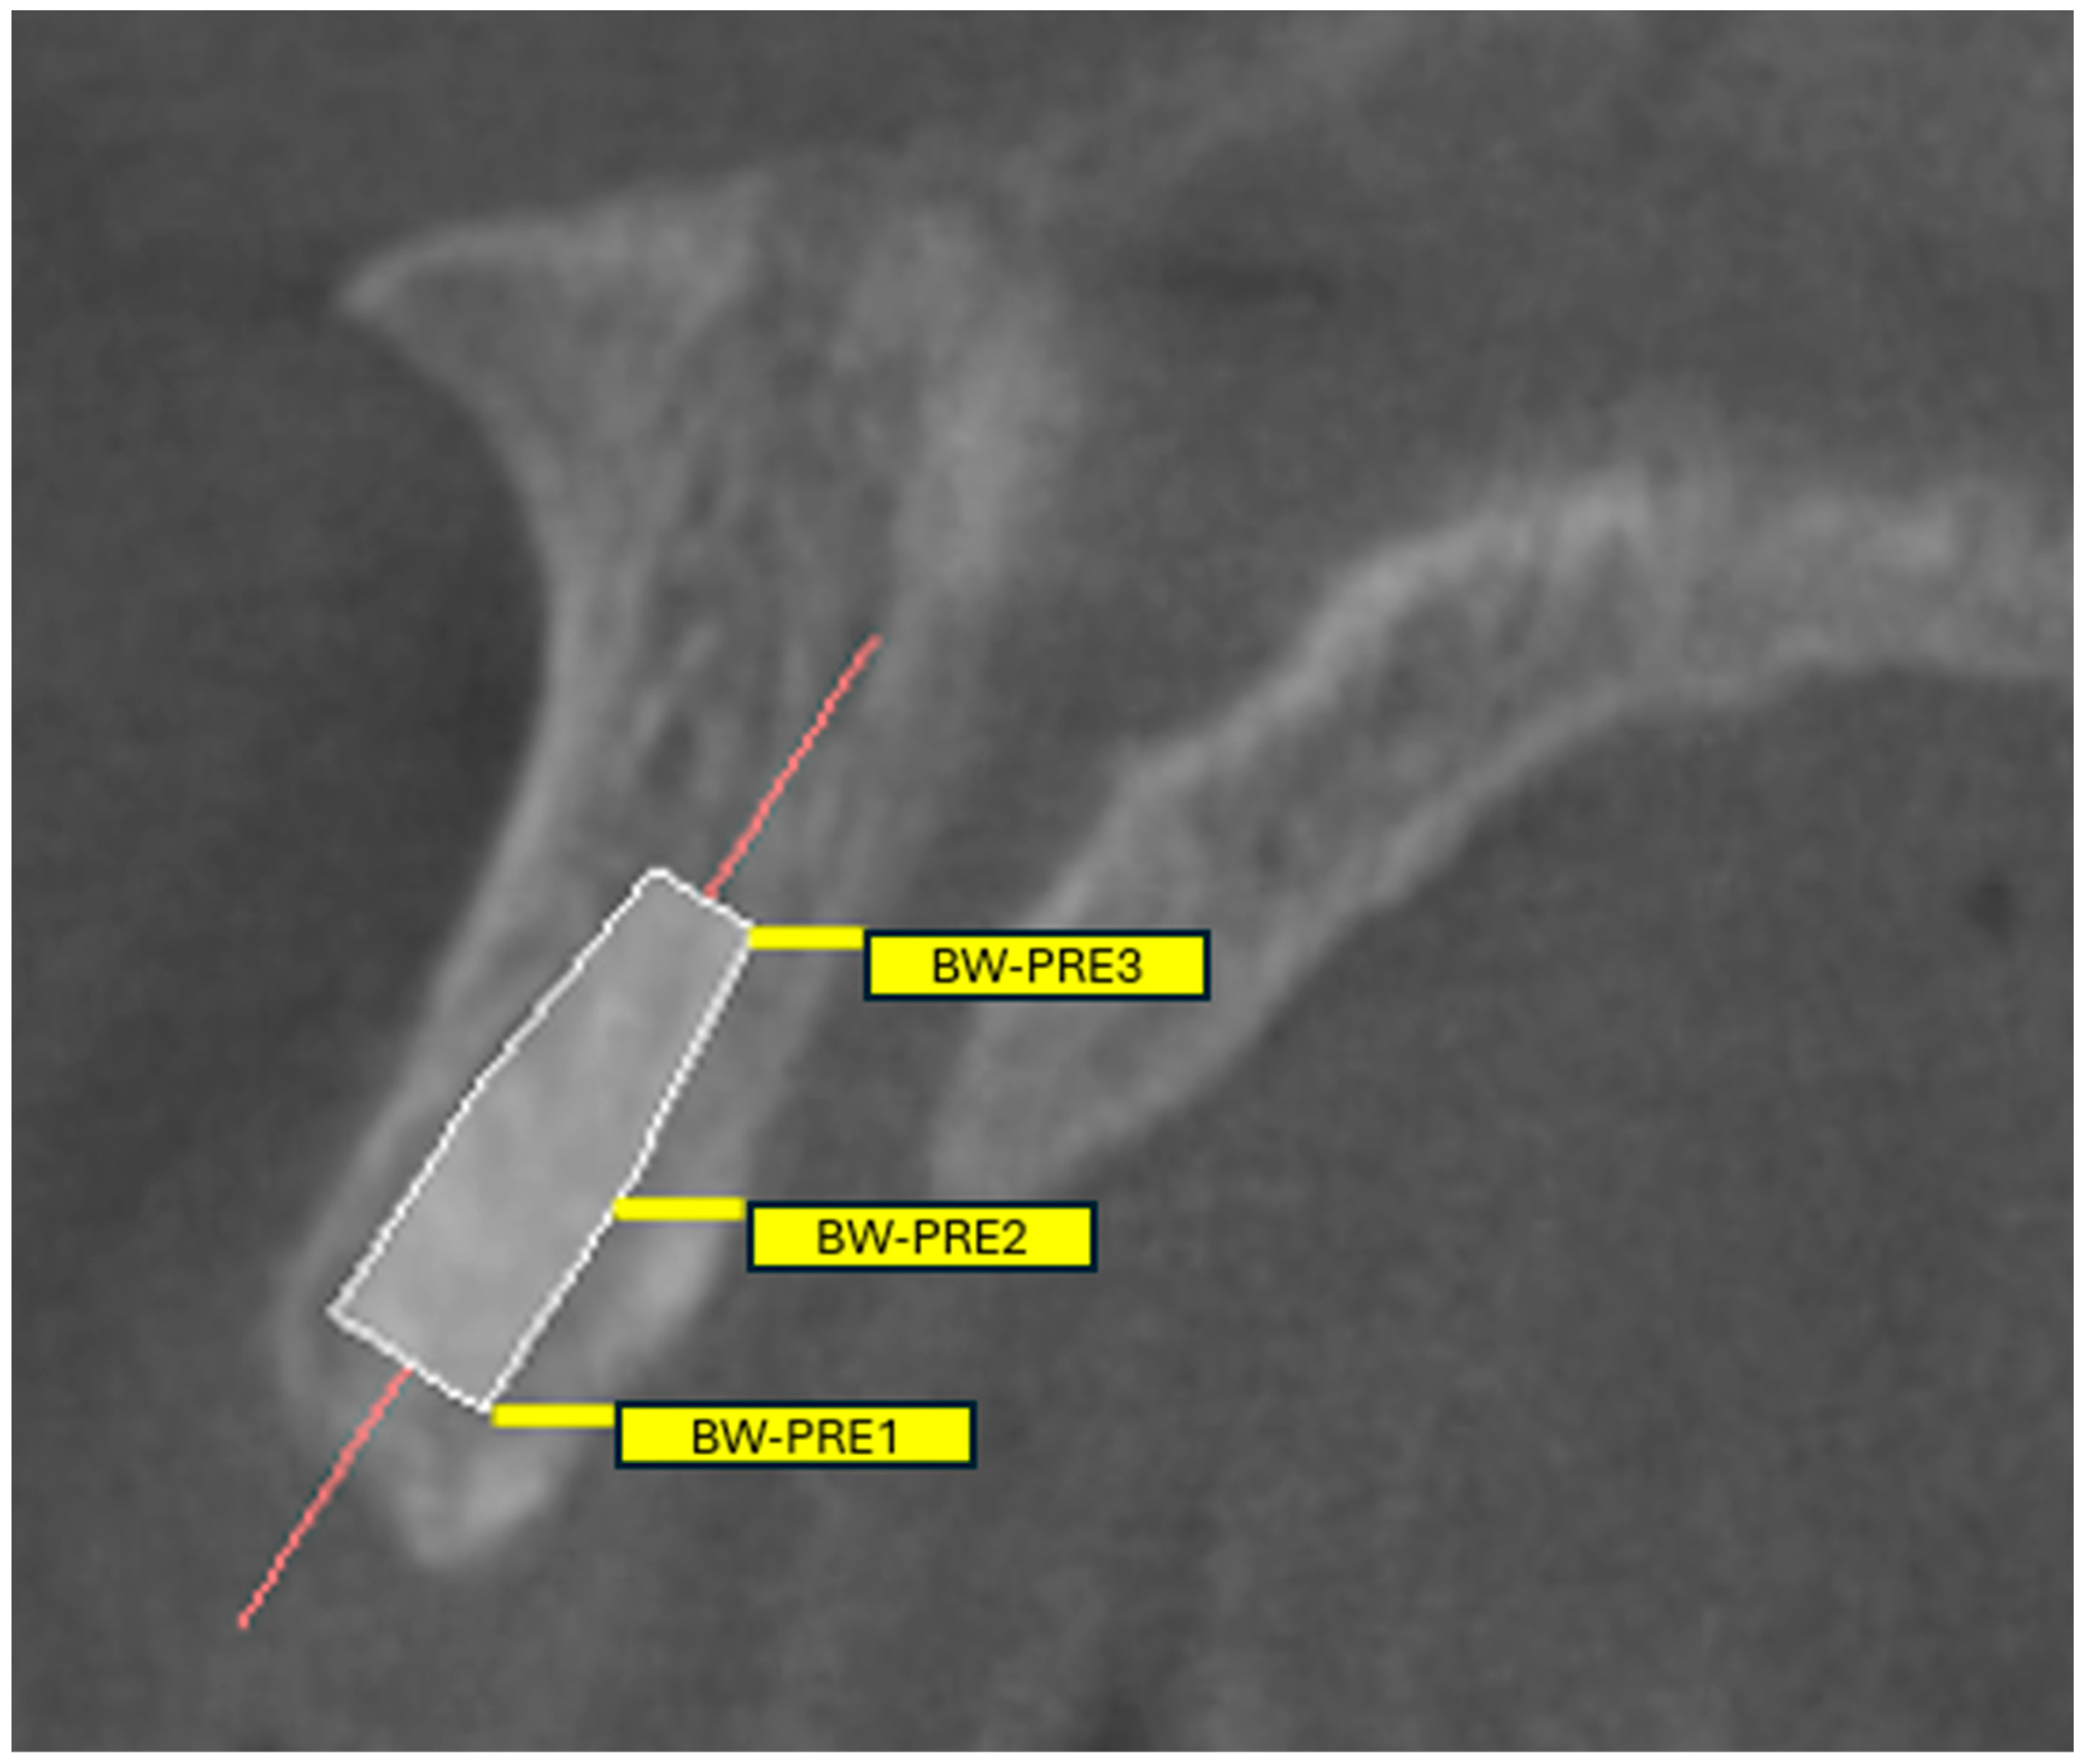

- Quantify proximity: Report Bw-pre 1/2/3 values and flag the lowest quartile—or a validated conservative threshold—as indicating heightened-risk proximity. Previous morphometric studies have demonstrated that the mean bone width between the central incisor root and the NPC ranges from approximately 1.4 mm at the coronal third to 3.2 mm at the apical third [9,10]. Accordingly, the risk of NPC perforation becomes clinically significant when the distance between the canal and the planned implant trajectory is less than 2 mm.

| Bw-pre 1 (mm) | 1.66 | 0.45 | |

| Bw-pre 2 (mm) | 2.53 | 0.58 | |

| Bw-pre 3 (mm) | 3.59 | 0.82 |